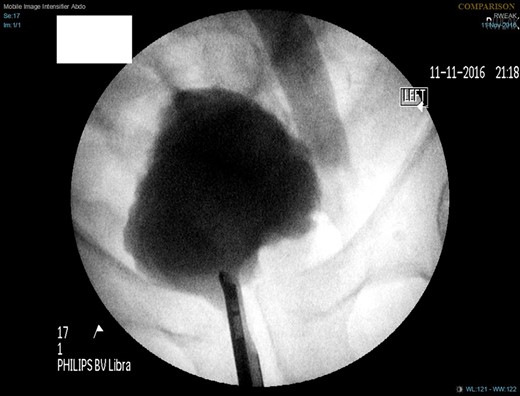

A week later, a left nephrostogram showed a capacious upper urinary tract with a deviated lower ureter which tapered in the pelvis with no filling defects seen above this level (Fig. 5). The appearances were in keeping with extrinsic compression. A week later, rigid cystoscopy, right-sided retrograde study, right JJ stent insertion and cystogram were performed. The left ureteric orifice could not be identified. The cystogram demonstrated no evidence of bladder herniation to the inguinal hernia (Fig. 6). Two months later, a non-contrast CT of the urinary tract demonstrated partial resolution of bilateral hydronephrosis, right-sided stent and left nephrostomy situated appropriately, persistence of left inguinoscrotal hernia and no other cause for ureteric compression. His eGFR was 34 mL/min when it was last checked a month prior to the non-contrast CT.

Left nephrostogram demonstrating tapering of the left ureter in the pelvis.